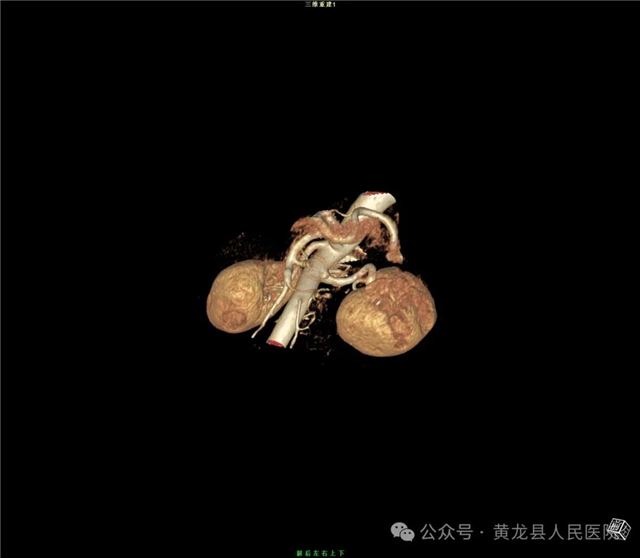

双肾增强CT

双肾VR